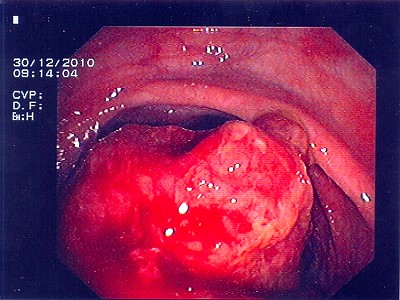

Abb. 3: Hier liegt das bösartige Gebilde exakt im Bereich des Überganges von Dick- zu Dünndarm. Die Umrisse des Überganges (bauhin'sche Klappe) kann man noch erkennen. Abb. 3: Hier liegt das bösartige Gebilde exakt im Bereich des Überganges von Dick- zu Dünndarm. Die Umrisse des Überganges (bauhin'sche Klappe) kann man noch erkennen.